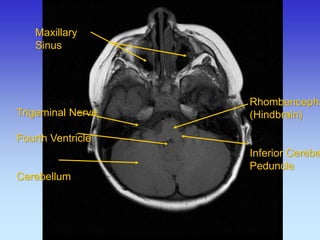

Maxillary Sinus

Trigeminal Nerve

Fourth Ventricle

Cerebellum

Rhombencephalon (Hindbrain) Inferior Cerebellar Peduncle